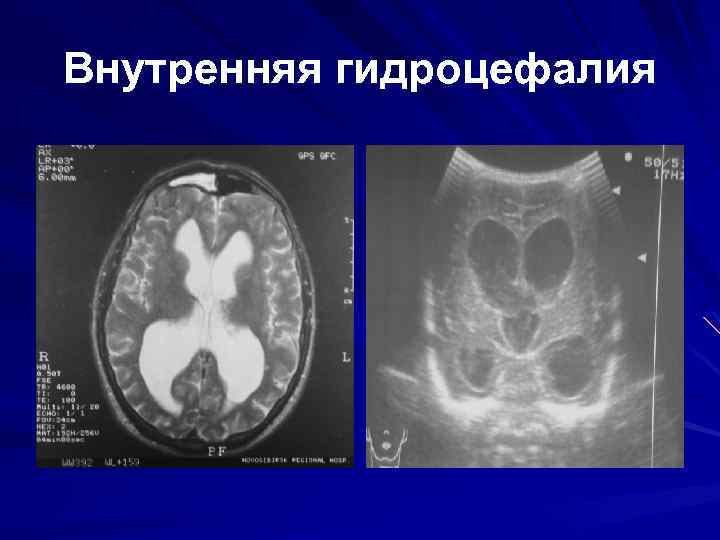

Признаки умеренно выраженной наружная

Признаки умеренно выраженной наружная 113 фото